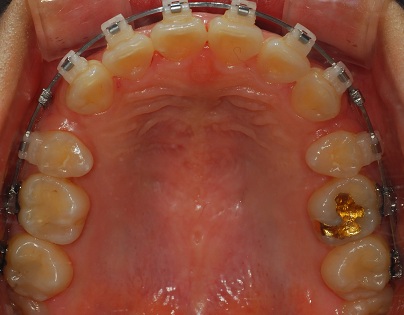

<상악 사진>

양쪽 발치공간의 차이가 나서 치과쌤이 치아 속도 맞추는데 열심히 하시고 있어용!